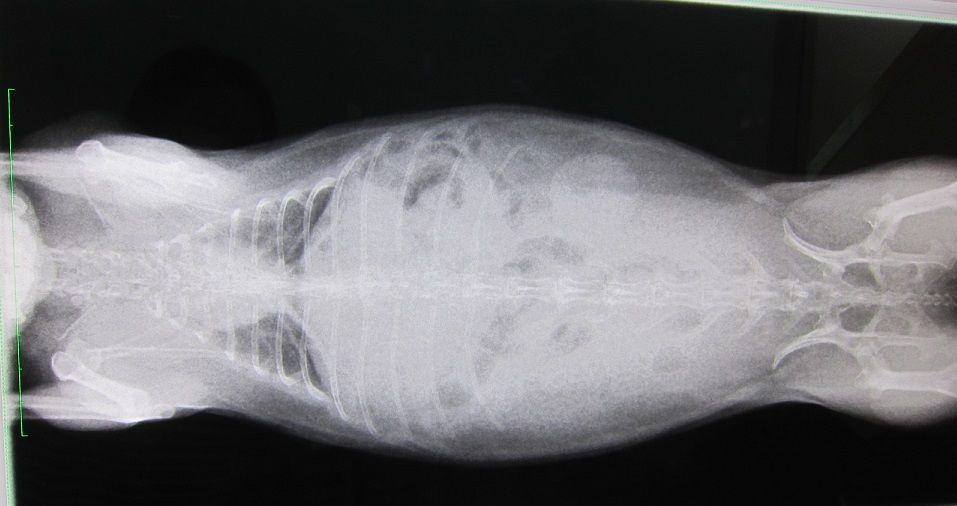

話を戻し、まずは切歯の状態から

臼歯のチェック

処置室でしそびれたということで、診察室で

抜歯した左側、舌に白いのが付着してたので、見当つけた場所を少し触ると膿が出た、と。

左側上の残る1本はかなり奥に位置し、

膿が出たのはそれより手前、歯のないところから。

上なので、左側の涙とも関係してるんだろうな…。